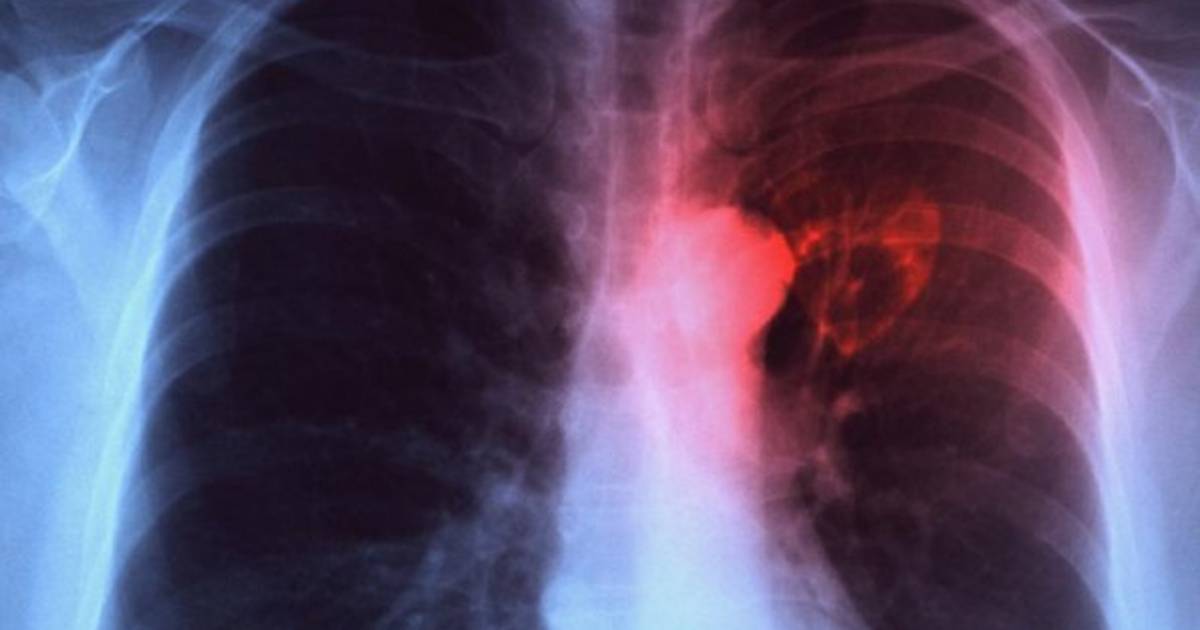

La enfermedad se transmite por el aire cuando las personas con tuberculosis pulmonar expulsan la bacteria que la causa, por ejemplo al toser

La tuberculosis es una enfermedad infecciosa que afecta típicamente a los pulmones pero que puede afectar a otros órganos.

La enfermedad se transmite por el aire cuando las personas con tuberculosis pulmonar expulsan la bacteria que la causa, por ejemplo al toser.